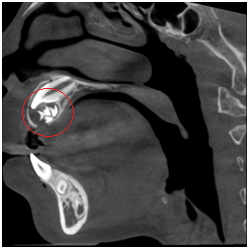

◆埋伏牙

◆牙瘤

◆由囊肿引起的骨质破坏